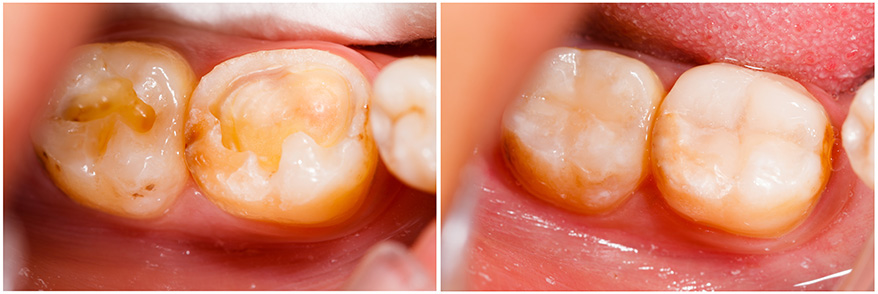

Las resinas dentales es la técnica correspondiente cuando lo que se busca es una opción conservadora y estética para dientes que han sufrido caries o pequeñas imperfecciones.

Los dientes deteriorados por caries requieren ser empastados, las obturaciones (empastes) que se realizan son blancas y muy resistentes a la masticación.

Los empastes blancos están compuestos por resina que es un material sintético que se endurece una vez que se le aplica luz halógena, los avances tecnológicos han hecho posible reconstruir dientes anteriores y empastar molares sin que se note, lográndose así estética y funcionalidad.

Cuando alguna persona presenta alguna cavidad en sus dientes, fisuras o restauraciones metálicas, las resinas dentales pueden ser una excelente y sana alternativa que tú y nuestro dentista deberán evaluar. Las restauraciones metálicas o amalgamas pueden ser fácilmente reemplazadas por este tipo de restauraciones estéticas.